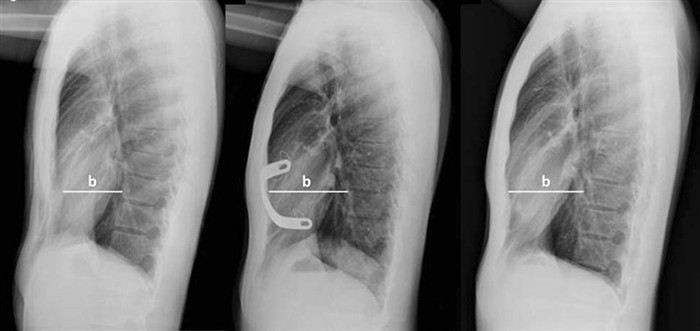

Процедура начинается с получения стандартного рентгеновского снимка, на котором четко видны изменения в костных и мягких тканях грудной клетки. Для измерения глубины деформации специалисты используют определенные ориентиры, например, расстояние между передней поверхностью грудной клетки и внутренними органами, а также угол искривления ребер. Это позволяет точно установить степень отклонения и классифицировать его по шкале, принятой в медицинской практике.

• Получение снимков в нескольких проекциях: для точности измерений часто требуется получить рентгеновские снимки в двух проекциях — боковой и прямой. Это позволяет лучше оценить трехмерное изменение формы грудной клетки.

• Определение глубины воронкообразной деформации: на основе снимков измеряется расстояние между позвоночником и центральной точкой грудной клетки в зоне максимальной воронковидной деформации. Также учитываются данные о наличии отклонений в реберных хрящах.

• Оценка симметрии грудной клетки: на снимках специалист обращает внимание на степень асимметрии, так как это может существенно влиять на выбор метода лечения или операции.